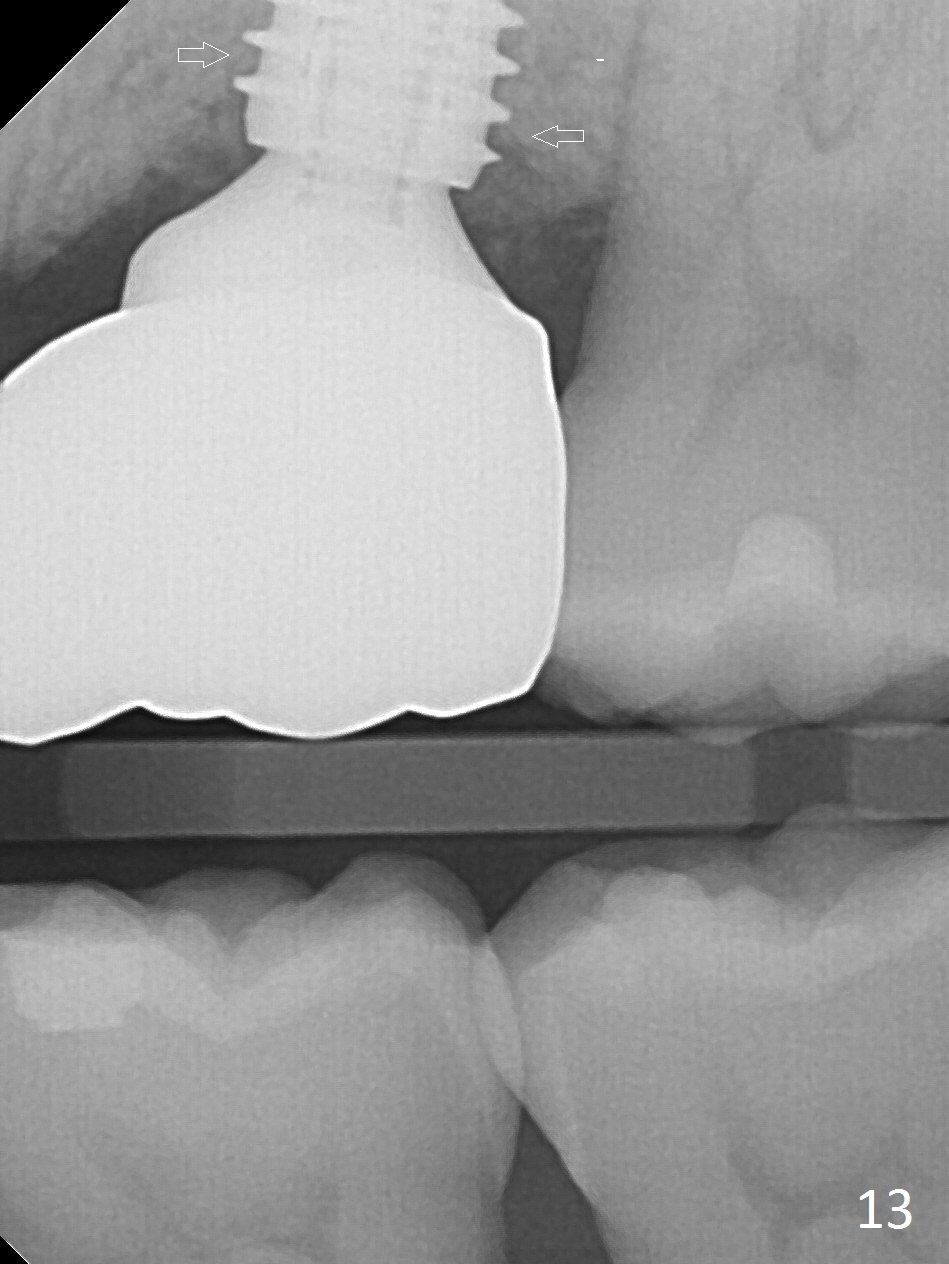

The patient experiences palatal gingival tenderness 5 months post cementation, probably due to loose proximal contacts and excessive use of floss. PA shows new normal bone next to the upper threads (Fig.12 arrow), while new less dense attached to the most coronal threads (*). BWs (Fig.13,14) shows that new bone has grown into the area between the most coronal 2 threads (arrows). When the crown and abutment are removed, the gingiva looks normal except minor laceration buccally. A 7.5x4 mm healing abutment is placed. If the infection resolves, pick up impression will be taken to add porcelain to the proximal surfaces to prevent food impaction.